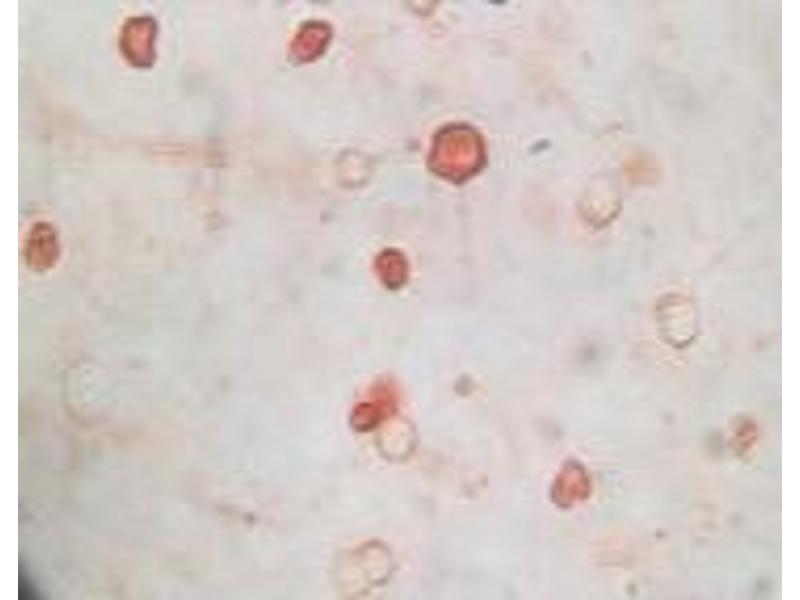

The 小鼠 单克隆 anti-KSHVK8a antibody (Clone 8C12G10G1) (ABIN2464074) specifically detects KSHVK8a in WB 和 ICC. The antibody is reactive with Human Herpesvirus 8 (HHV-8) samples.

Western Blotting (WB), Immunocytochemistry (ICC)

ICC:Dilution 1:50 - 1:100